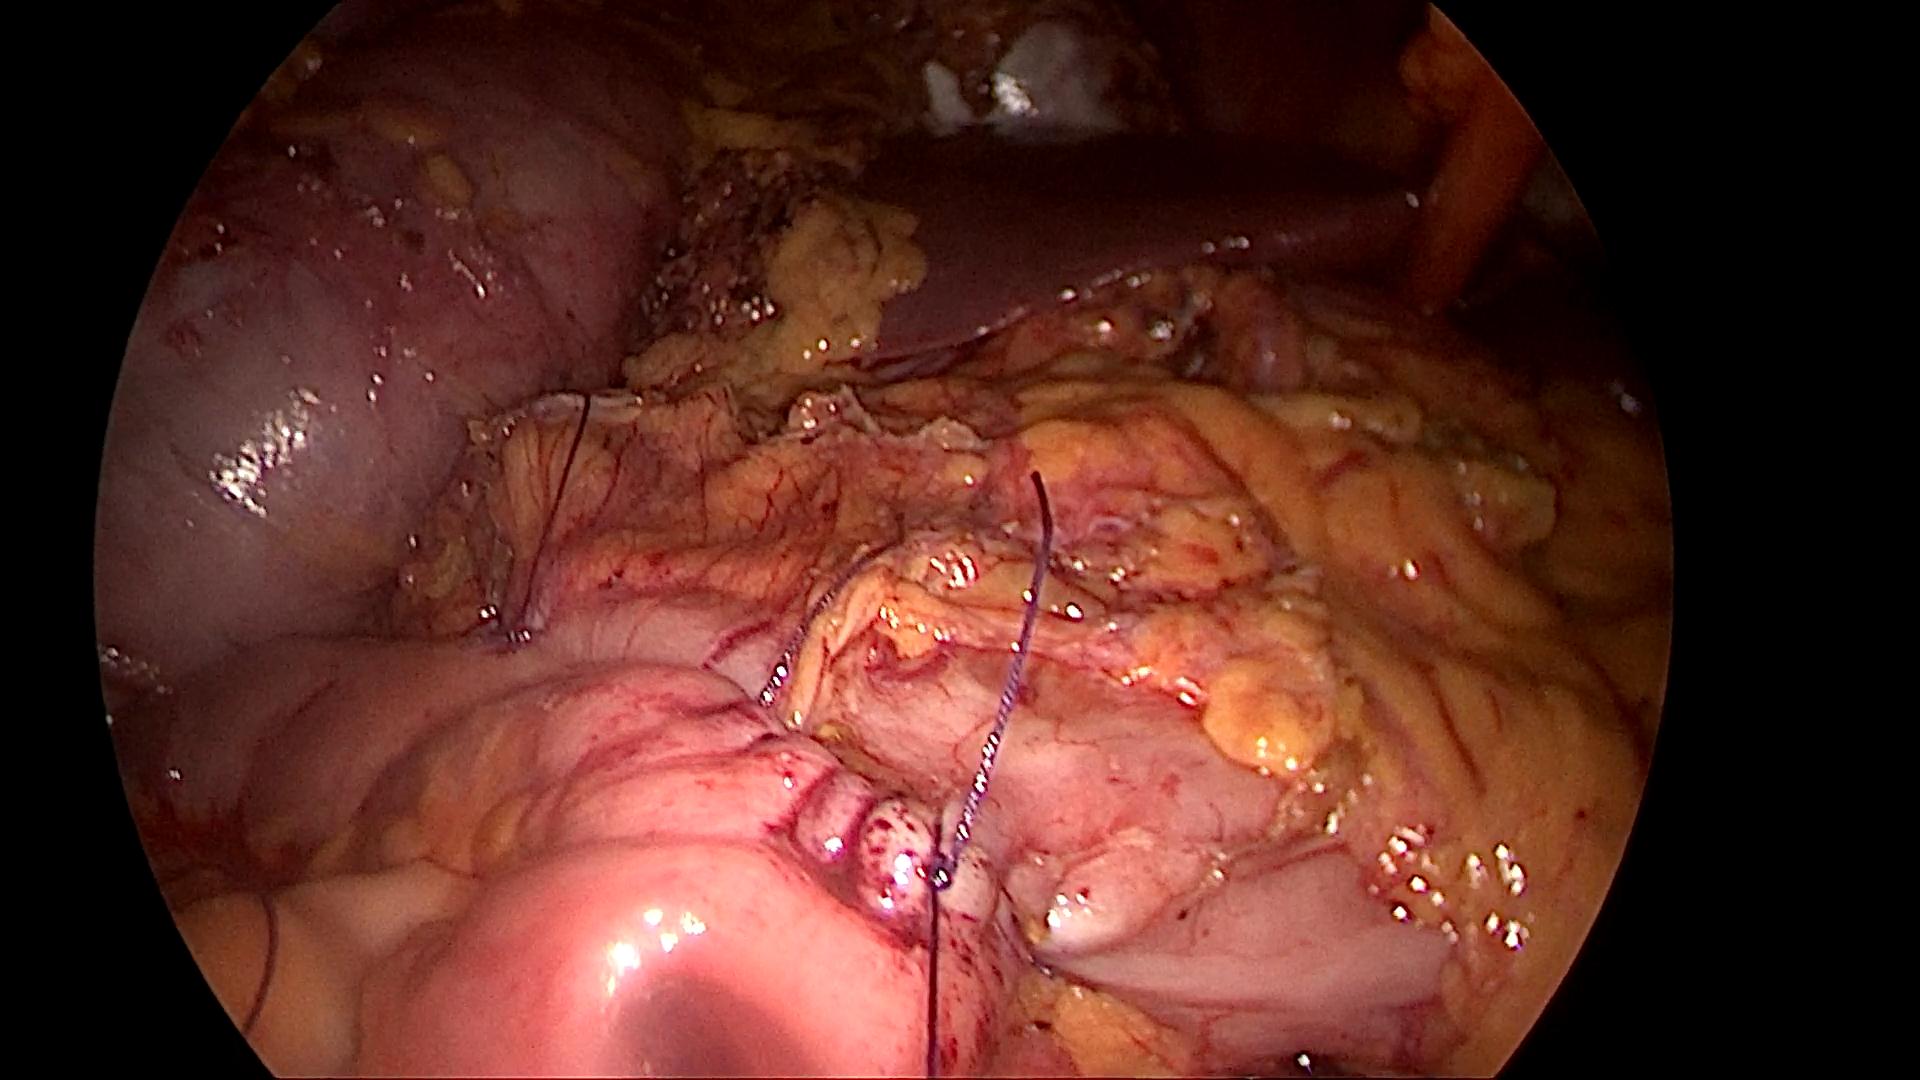

Phẫu thuật nội soi hoàn toàn cắt đoạn đại tràng góc lách, miệng nối đại tràng ngang – đại tràng trái được thực hiện trong cơ thể bằng dụng cụ ghim cắt thẳng kết hợp khâu tay đóng lỗ đặt máy (BN Lê thị V)

Với phẫu thuật nội soi hoàn toàn điều trị ung thư đại tràng: sau khi đoạn đại tràng có u cùng toàn bộ mạc treo, hạch được cắt; miệng nối trong cơ thể được thực hiện theo kiểu bên – bên hoặc tận – tận chức năng. Các miệng nối trên có thể được thực hiện bằng dụng cụ ghim cắt nối, có thể kết hợp với khâu tay hoặc khâu tay toàn bộ tùy thuộc phẫu thuật viên và trường hợp cụ thể.